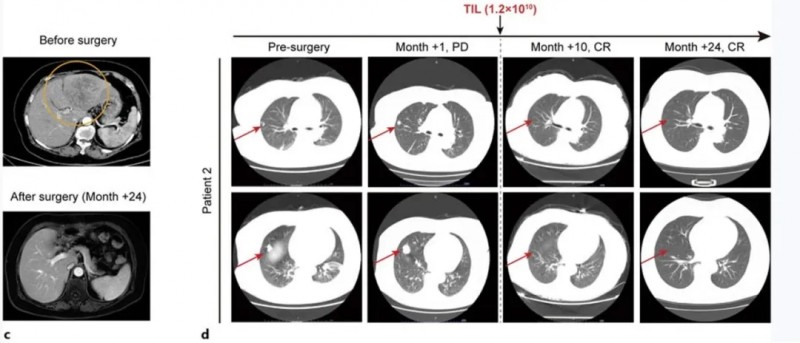

患者2是一位67岁女性,因肿瘤破裂出血接受经肝动脉栓塞术后1周入院。CT显示肝左叶147×79mm混合信号肿块,双肺存在多个散在结节,右肺中叶最大结节直径18mm。甲胎蛋白水平14,529ng/mL,确诊为HBV相关性肝细胞癌,BCLC分期为C期。

该患者入组后,接受了姑息性左半肝切除术,在TIL培养29天后,先后接受淋巴细胞清除治疗+自体TIL细胞单次输注+IL-2治疗+特瑞普利单抗治疗(18个疗程)。

结果显示:肝切除术后1个月,肺转移灶进展,右肺结节增大至25mm;接受TIL输注及常规抗PD-1治疗后,术后10个月肺病灶完全消失,至今24个月仍保持无瘤状态(详见下图c、d)。

▲图源“Liver Cancer”,版权归原作者所有,如无意中侵犯了知识产权,请联系我们删除